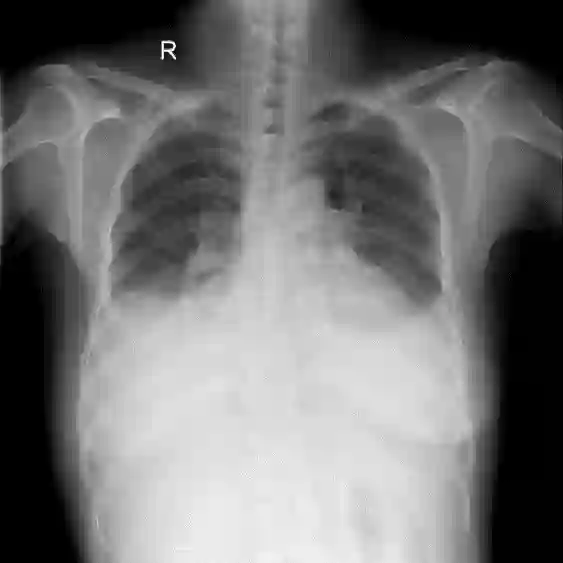

Chest X-ray (CXR) is the most typical diagnostic X-ray examination for screening various thoracic diseases. Automatically localizing lesions from CXR is promising for alleviating radiologists' reading burden. However, CXR datasets are often with massive image-level annotations and scarce lesion-level annotations, and more often, without annotations. Thus far, unifying different supervision granularities to develop thoracic disease detection algorithms has not been comprehensively addressed. In this paper, we present OXnet, the first deep omni-supervised thoracic disease detection network to our best knowledge that uses as much available supervision as possible for CXR diagnosis. We first introduce supervised learning via a one-stage detection model. Then, we inject a global classification head to the detection model and propose dual attention alignment to guide the global gradient to the local detection branch, which enables learning lesion detection from image-level annotations. We also impose intra-class compactness and inter-class separability with global prototype alignment to further enhance the global information learning. Moreover, we leverage a soft focal loss to distill the soft pseudo-labels of unlabeled data generated by a teacher model. Extensive experiments on a large-scale chest X-ray dataset show the proposed OXnet outperforms competitive methods with significant margins. Further, we investigate omni-supervision under various annotation granularities and corroborate OXnet is a promising choice to mitigate the plight of annotation shortage for medical image diagnosis.